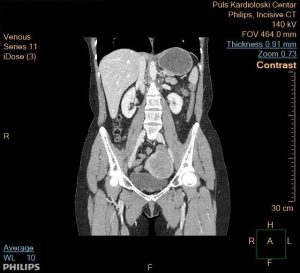

III.Ikoreshwa rya Contraste muri CT Scan

Contraste ni umuti (contrast agent/dye) winjizwa mu mubiri kugira ngo utange ishusho irambuye kurusha isanzwe. CT Scan ishobora gukorwa idafite contraste cyangwa itayifite. Contraste ya CT Scan ikozwe mu miti ifite iodine (IV) cyangwa barium (oral/rectal),Iodine ikoreshwa cyane mu mitsi n’utunyangingo, naho barium ikoreshwa mu gifu n’amara.

Impamvu contraste ikoreshwa

– Kwerekana neza imitsi y’amaraso (blood vessels): contraste ituma imitsi igaragara neza, bigafasha gusuzuma ibibazo nk’ifunga ry’imitsi cyangwa aneurysm.

– Kwerekana neza utunyangingo (soft tissues): utunyangingo nk’umwijima, impyiko, n’umutima bigaragara neza iyo hifashishijwe contraste.

– Gusuzuma indwara zifata ingingo z’imbere: nka cancer, infections, cyangwa ibibyimba (tumors). Contraste ituma bigaragara neza ku mashusho.

– Kugenzura imikorere y’impyiko n’umwijima: uburyo contraste isohoka mu mubiri bushobora kwerekana uko impyiko n’umwijima bikora.

– Kwerekana neza ibikomere: nko kumenya aho amaraso yamenetse cyangwa aho hari ibikomere mu mubiri.

Mu magambo magufi: Contraste muri CT Scan ikoreshwa kugira ngo amashusho agaragaze neza imitsi, utunyangingo, n’ibibyimba, bigafasha muganga kubona amakuru arambuye kurusha CT Scan isanzwe.